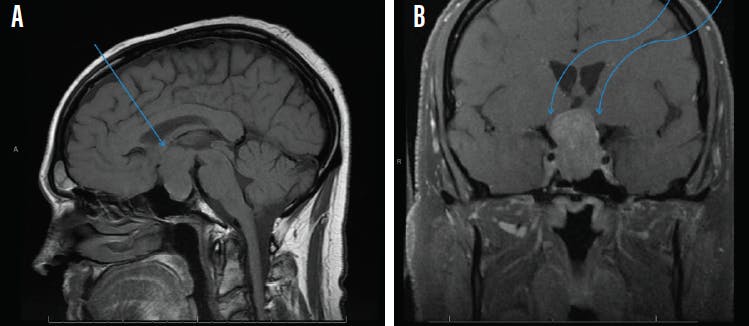

MRI of the brain and/or orbits, with and without contrast, with attention to the sella is the recommended medium for diagnosis (Figure 2). A patient with a confirmed pituitary macroadenoma should be referred to both neurosurgery and endocrinology. Asymptomatic patients with incidental macroadenomas should receive continued ophthalmologic surveillance because any new visual symptoms strongly indicate a need for surgical intervention. Although there are no established guidelines for the length of ophthalmologic follow-up, lesion size and a progression of visual field defects should inform decisions regarding timeline.

<p>Figure 2. Sagittal midline precontrast T1-weighted MRI showing enlargement of the sella turcica and superior extension of a pituitary macroadenoma (arrow, A). Coronal T1-weighted MRI with contrast showing the optic chiasm stretched and compressed over the mass (arrows, B).</p>

Figure 2. Sagittal midline precontrast T1-weighted MRI showing enlargement of the sella turcica and superior extension of a pituitary macroadenoma (arrow, A). Coronal T1-weighted MRI with contrast showing the optic chiasm stretched and compressed over the mass (arrows, B).